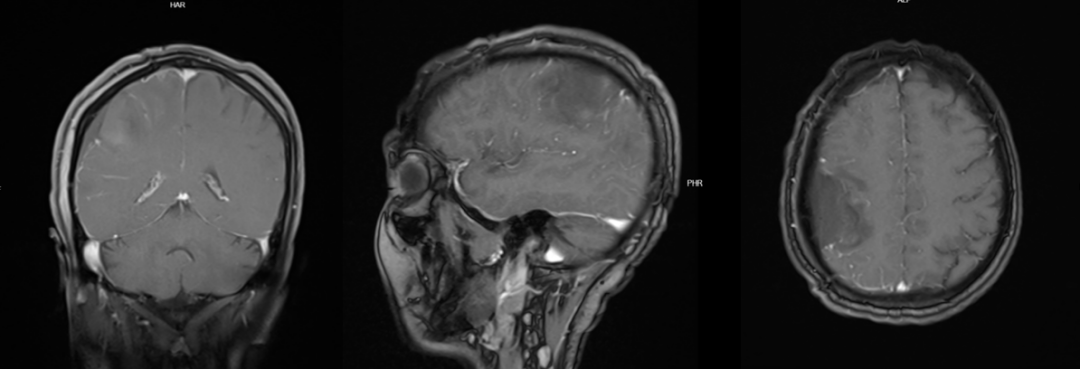

术前MRI:

术后磁共振:

图30